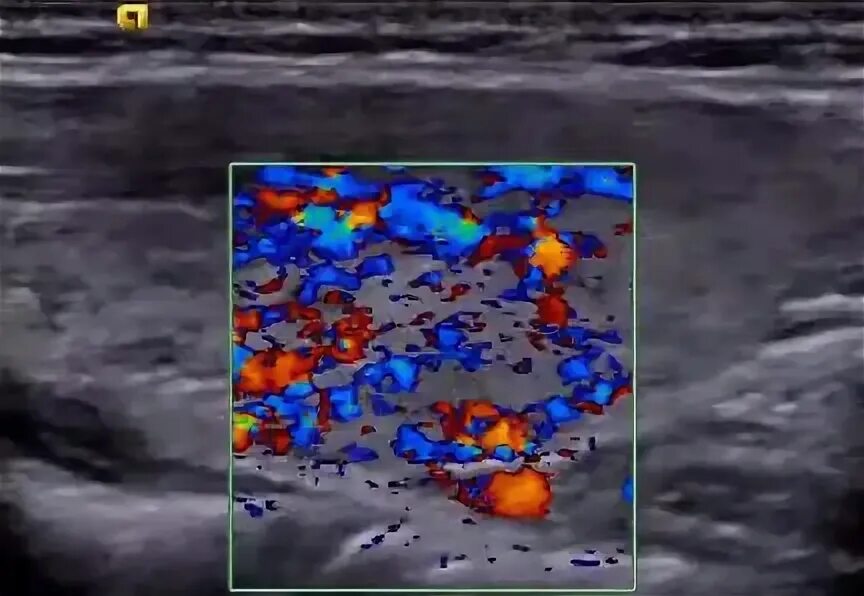

На фоне диффузных изменений